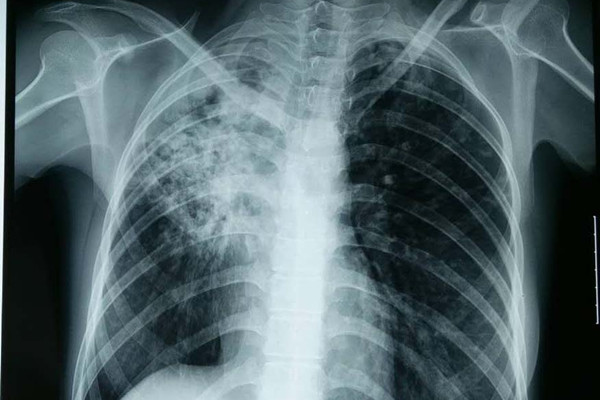

结核复发后,症状和初期患病无明显差别,常见症状有咳嗽、咳痰、咯血、胸痛,低热、盗汗、乏力等症状,胸部影像学检查会发现原有病灶增大或在原有病灶的基础上出现新病灶、新发空洞或原有空洞增大、新出现纵隔淋巴结肿大 或出现胸腔积液等征象,查痰有可能再次为阳性结果。